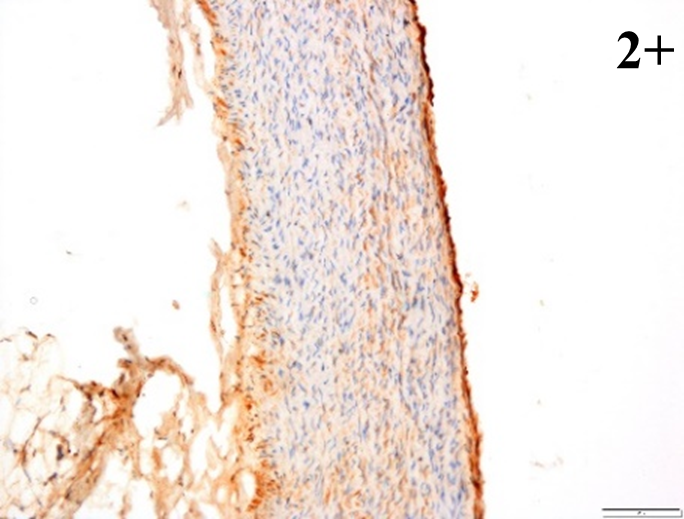

According to the percentage endothelial staining of cells, semi-quantitative

scores were applied. Score: 0 (negative); 1+ (1–10% positive cells); 2+

(11–25% positive cells) and 3+ (